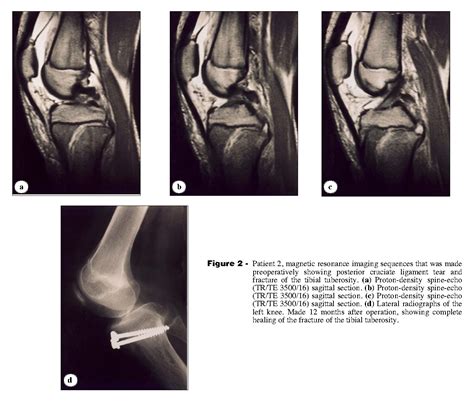

To confirm the diagnosis, medical professionals typically utilize imaging studies. X-rays are the gold standard for visualizing the displaced bone fragment and determining the severity of the fracture. In more complex or comminuted cases, an MRI may be ordered to assess the condition of the surrounding soft tissues, including the patellar tendon and menisci.

Orthopedic surgeons often categorize these injuries based on the Ogden classification system, which helps guide treatment decisions. This classification ranges from simple, non-displaced fractures to complex injuries that extend into the knee joint.

Type Severity Description Typical Treatment

Type I Small fracture at the distal part of the tuberosity. Conservative (casting)

Type II Fracture extends through the secondary ossification center. Surgery often required

Type III Fracture extends into the articular surface of the knee. Surgical intervention

However, if the fragment is displaced or if the knee joint is compromised, surgical intervention is mandatory. The surgical procedure typically involves:

• Open Reduction Internal Fixation (ORIF): The surgeon makes an incision to visualize the bone fragment.

• Hardware Placement: The loose piece of bone is secured back to the main tibia using screws, wires, or specialized anchors.